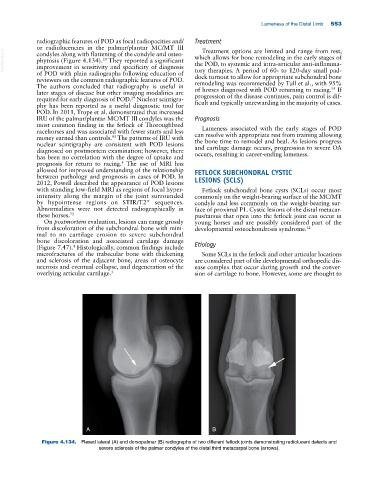

Figure 4.134. Flexed lateral (A) and dorsopalmar (B) radiographs of two different fetlock joints demonstrating radiolucent defects and

severe sclerosis of the palmar condyles of the distal third metacarpal bone (arrows).